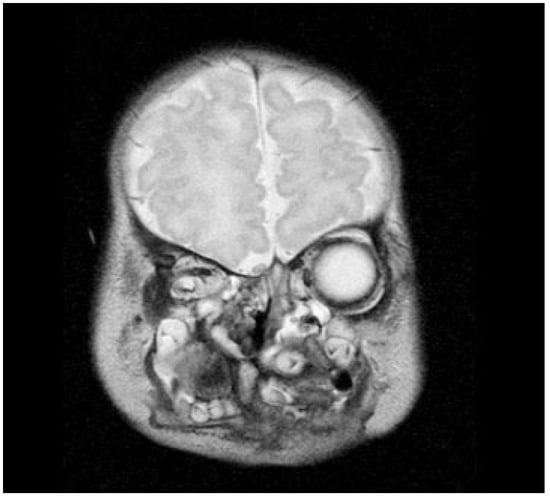

Neonatal examination exhibited frontonasal dysmorphism (bifid anterior cranium, hypertelorism, blepharophimosis, broad nasal bridge, and broad nasal tip), low implantation of the ears, a short neck, bifid and protrusive tongue covered with lanugo, inferior lip and buccolabial sulci malformation, macrostomia, microretrognathia, and except for a small slit in the lateral regions, through which only the end of alveolar ridge could be seen, the mandible and maxilla were fused at gum level (Figure 2). Nasoendoscopy showed complete cleft of the median palate. Magnetic resonance imaging (MRI) revealed orbital hypertelorism, midline cranial cleft ending just superior to the nasal dorsum, agenesis of the corpus callosum, and maxillomandibular fusion (Figure 3 and Figure 4).

Figure 3.

Coronal view on magnetic resonance imaging confirms the midline cranial cleft.

Figure 4.

Magnetic resonance image showing the maxillomandibular bony fusion.